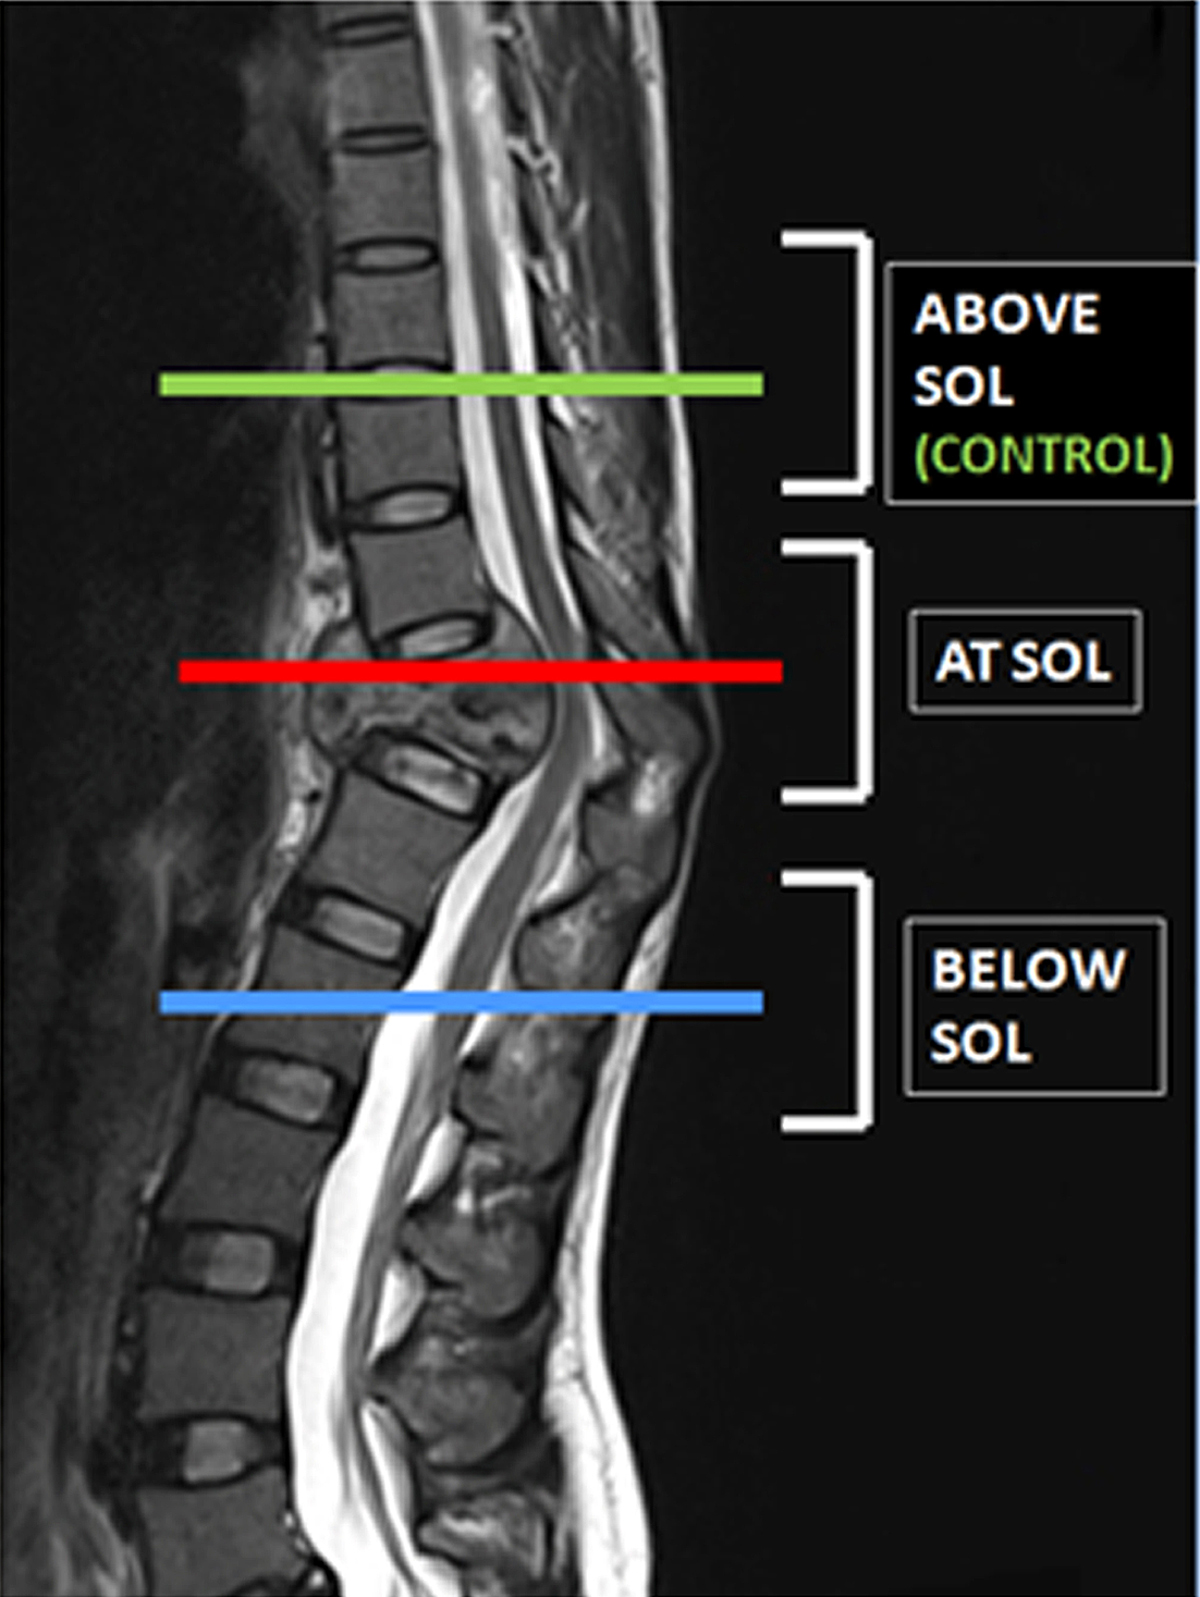

Figure 3.

Levels of site of lesions (SOL) as marked on a T2 sagittal MRI image.